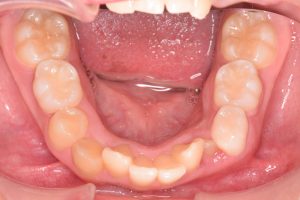

2期治療開始時(2023年7月)と装置撤去時(2025年9月)の写真です。

上あご